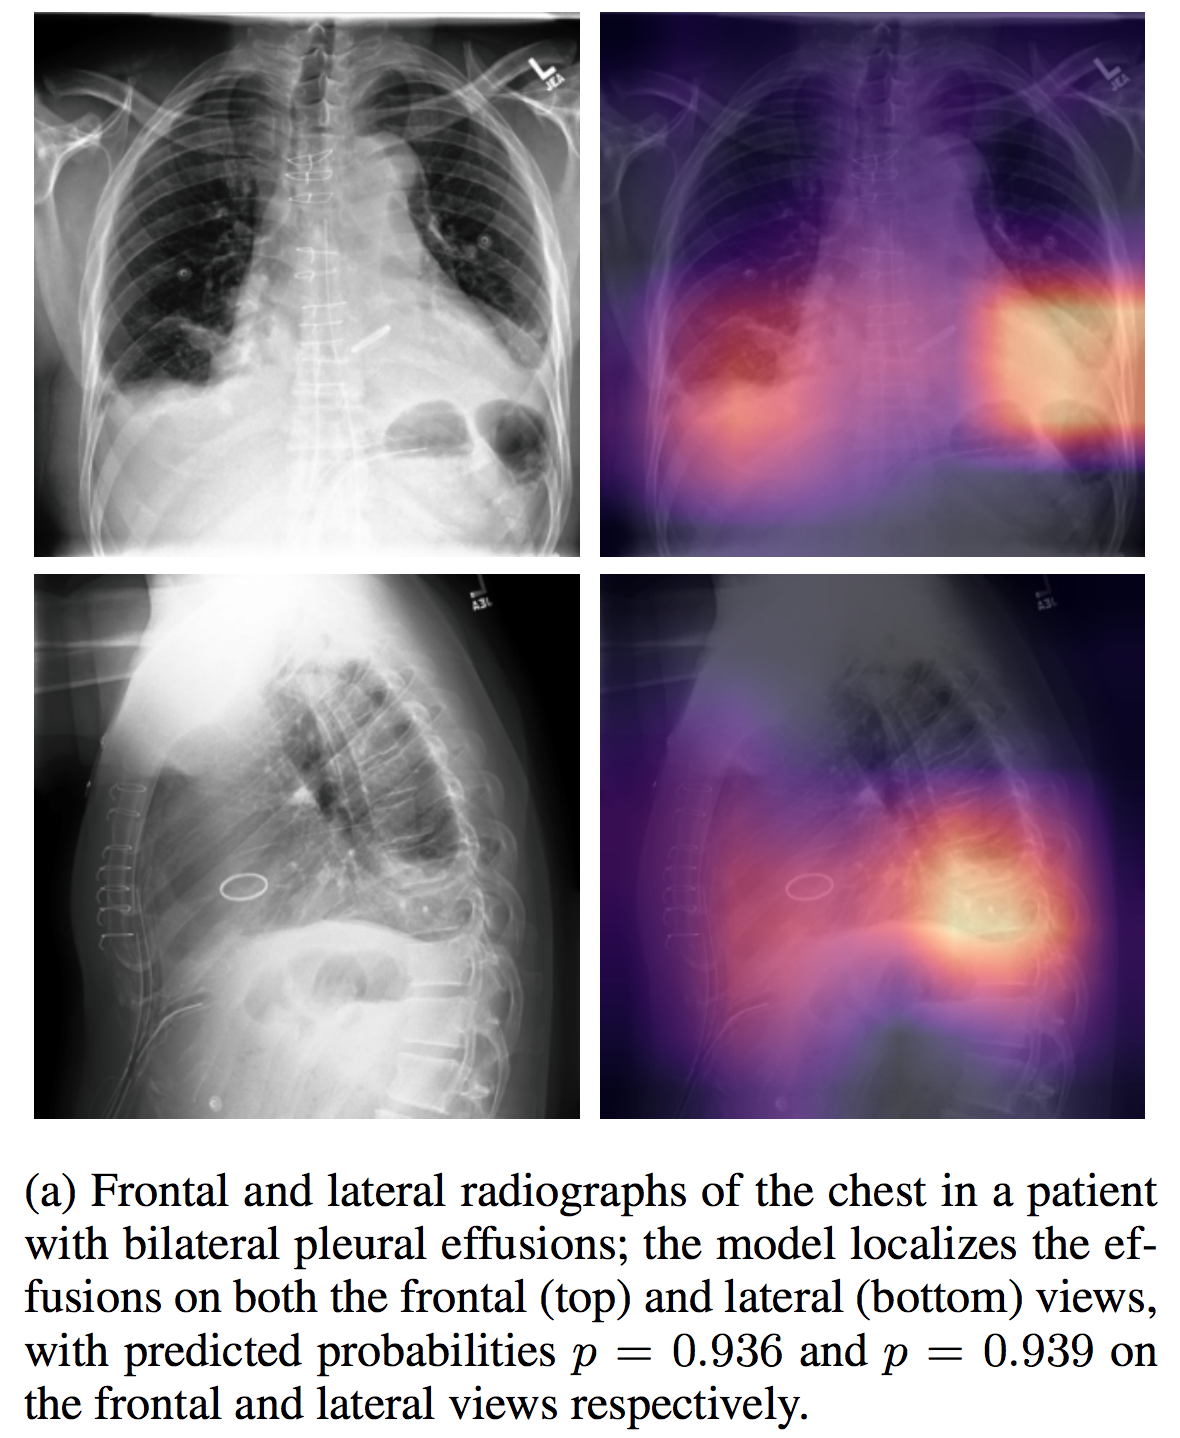

CheXpert

| 名称 | 标注内容 | 类型 | 模态 | 数量 | 标签格式 | 文件格式 |

|---|---|---|---|---|---|---|

| CheXpert |

介绍论文: CheXpert: A Large Chest Radiograph Dataset with Uncertainty Labels and Expert Comparison